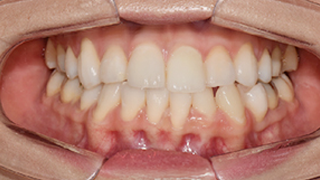

한눈에 보는

치아교정 전후사진